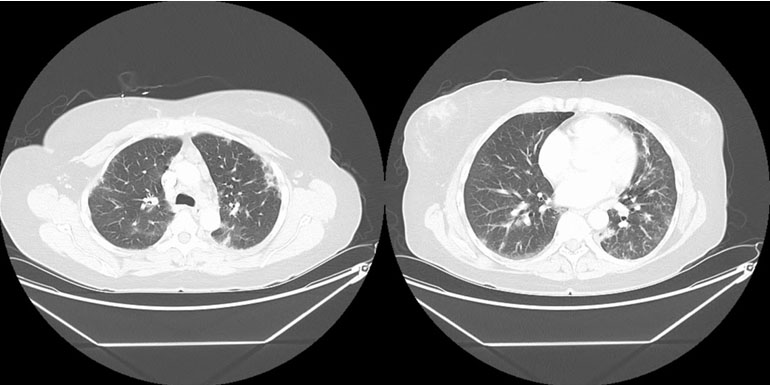

Radiologist: Computed tomography (CT) of the chest with contrast (Figure 1) showed multifocal groundglass opacities that were re-demonstrated in both lungs. These were weighted in the lower lobes, left worse than right. Additional lymphadenopathy included perivascular lymph nodes with one selectively measuring 0.6 cm short axis. Multiple lymph nodes demonstrated abnormal-rounded morphology. Bronchoscopy data might be informative.

Figure 1: Computed tomography (CT) of the chest with contrast during admission—multifocal ground-glass opacities in bilateral lower lobes, left worse than right. Additional abnormal-rounded morphologic lymphadenopathy including perivascular lymph nodes with one selectively measuring 0.6 cm short axis.

The diagnosis of ABPA was entertained due to the patient’s recurrent asthma exacerbations, eosinophilia, pulmonary consolidation with ground glass opacities, and bronchiectatic changes. Allergic bronchopulmonary aspergillosis was further supported after the patient completed a course of antibiotics without significant improvement, along with the lack of improvement in eosinophilia with prednisone. On further workup, however, several key factors helped rule this out as a possible diagnosis. These factors include, but are not limited to, negative Aspergillus antibodies, IgE < 1000 without meeting all other diagnostic criteria (Table 1), and lack of bronchial wall thickening on imaging (Figure 1). This diagnosis was effectively ruled out at the time of these findings.

Sjögren’s syndrome was first considered after initial workup by pulmonology when labs revealed a positive RF and Sjögren SSA antibody (Table 1). Although SSA antibodies are not sufficient to make the diagnosis, SS was taken into consideration due to the patient’s respiratory symptoms mimicking that of pulmonary involvement in SS. Additionally, various features overlapped with regard to imaging. Such features include bronchiectasis, ground glass opacities, and consolidation (Figure 1 and Figure 2). Nevertheless, these pulmonary findings are nonspecific, and SS should not be diagnosed solely based on positive antibodies. With the patient lacking supportive features of ocular or oral dryness, SS is unlikely. If these characteristic symptoms develop, additional workup with Schirmer test or ultrasound may be indicated for further analysis.